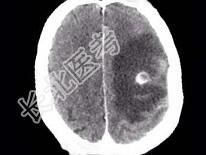

- 单项选择题男,58岁, 头痛、恶心、行走不稳,肺和脑CT检查如图, 最可能的诊断为 ( )

C、肺癌脑转移